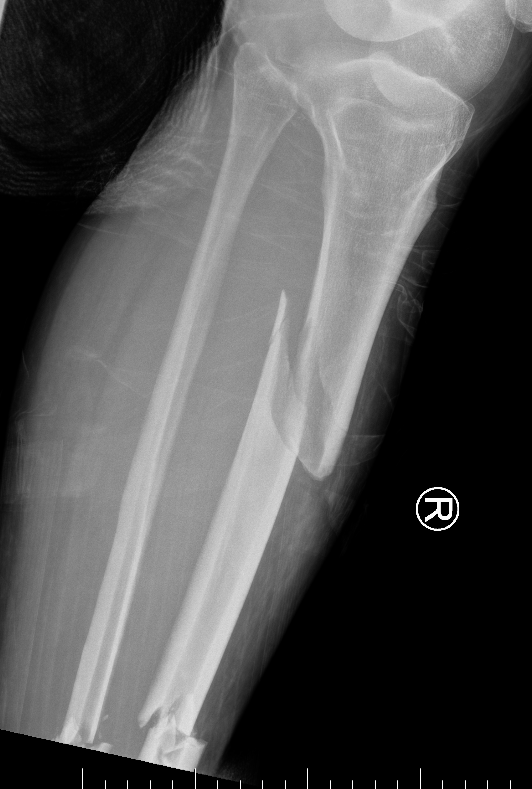

Segmental shaft fractures

Segmental tibia 1Segmental tibia 2

Corey et al J Orthop Trauma 2018

- 95 treated with IMN

- nonunion rate 10%

https://pubmed.ncbi.nlm.nih.gov/29432320/